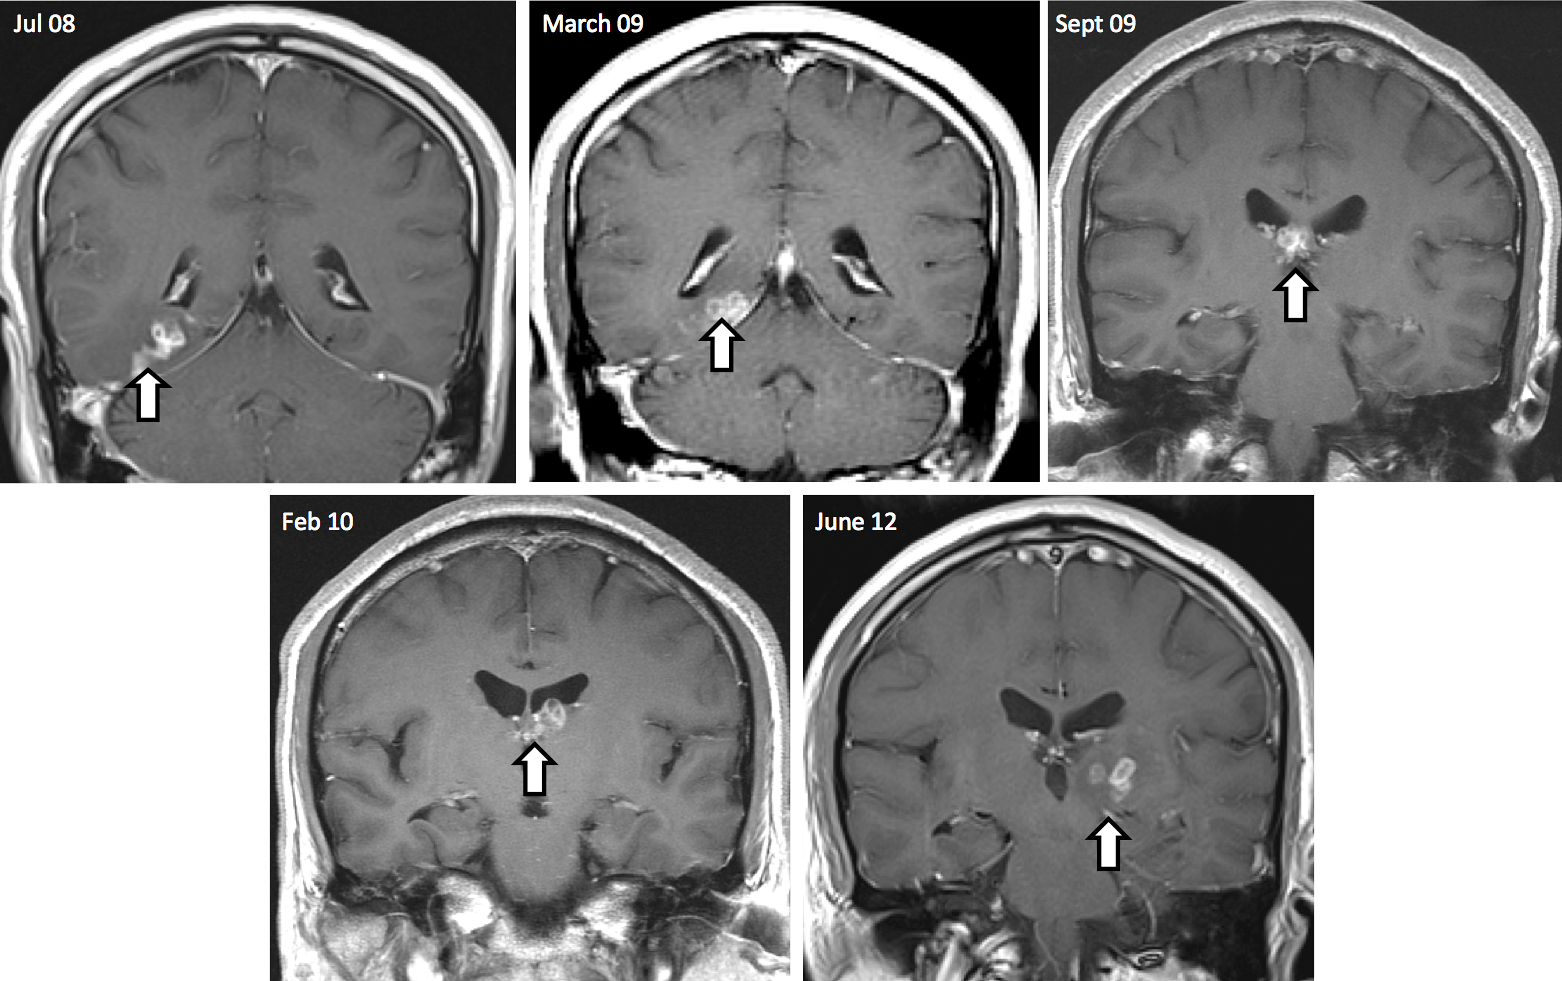

Before the 1cm-long parasite was diagnosed and successfully removed by surgery, it had travelled 5cm from the right side of the brain to the left. The tapeworm was placed on a histology slide by the hospital to confirm the clinical diagnosis. The patient is now systemically well.

“We did not expect to see an infection of this kind in the UK, but global travel means that unfamiliar parasites do sometimes appear. We can now diagnose sparganosis using MRI scans, but this does not give us the information we need to identify the exact tapeworm species and its vulnerabilities. Our work shows that, even with only tiny amounts of DNA from clinical samples, we can find out all we need to identify and characterise the parasite.